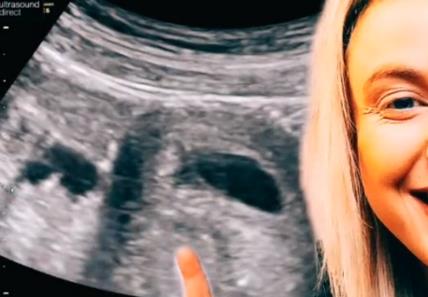

REKLI SU MI DA NOSIM BLIZANCE, A ONDA JE DOKTORKA POČELA DA VRIŠTI OD SMEHA: Pogledajte hit snimak sa ultrazvuka! VIDEO

Reaguj

Komentariši